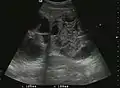

HCC appearance on 2D ultrasound is that of a solid tumor, with imprecise delineation, with heterogeneous structure, uni- or multilocular (encephaloid form). An "infiltrative" type is also described which is difficult to discriminate from liver nodular reconstruction in cirrhosis. Typically HCC invades liver vessels, primarily the portal veins but also the hepatic veins . Doppler examination detects a high speed arterial flow and low impedance index (correlated with described changes in tumor angiogenesis). The spatial distribution of the vessels is irregular, disordered. CEUS examination shows hyperenhancement of the lesion during the arterial phase. During the portal venous phase there is a specific "wash out" of ultrasound contrast agent (UCA) and the tumor appears hypoechoic during the late phase. Poorly differentiated tumors may have a stronger wash out leading to an isoechoic appearance to the liver parenchyma during portal venous phase. This appearance was found in approx. 30% of cases. The described changes have diagnostic value in liver nodules larger than 2 cm.